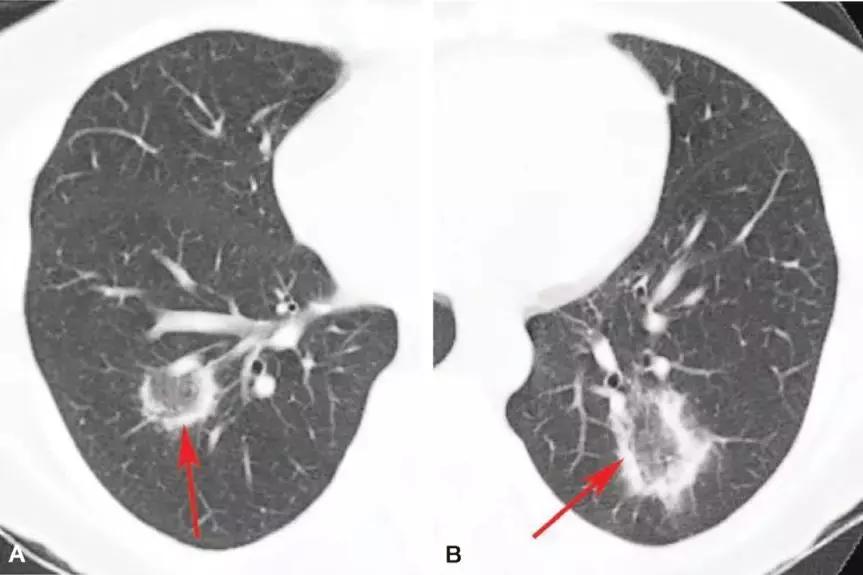

结节或团块(需要和肿瘤鉴别):

4、机化性肺炎的鉴别

究竟是不是机化性肺炎,首先影像学有提示,尤其表现为实变;确诊需要病理学检查——机化是否为主要表现。确认为机化性肺炎后,还要判断它是原发还是继发的。

孤立性肺炎型:则需要与结核、肺部肿瘤等进行鉴别。